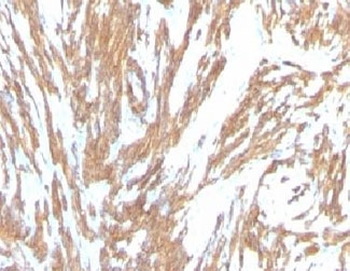

IHC: Formalin-fixed, paraffin-embedded Leiomyosarcoma stained with Smooth Muscle Actin antibody (clone SPM332).